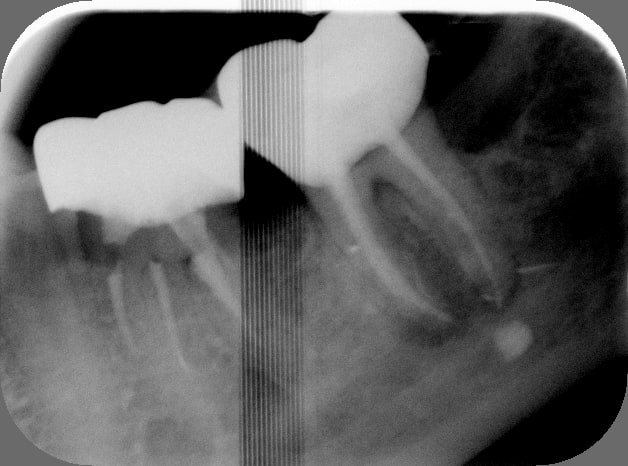

Putain de sa mère, j'ai pété un R25 à l'apex du 5°canal... Canal lingual en C, j'en étais au 8° canal pour l'instrument, j'aurai pas dû être joueur.

1h en comptant la dépose de la couronne, la RCR et la pro en bloc technique.

Avant t89ni5 - Eugenol

Apr s oqfrgc - Eugenol

Photo dentiste etgjzw - Eugenol